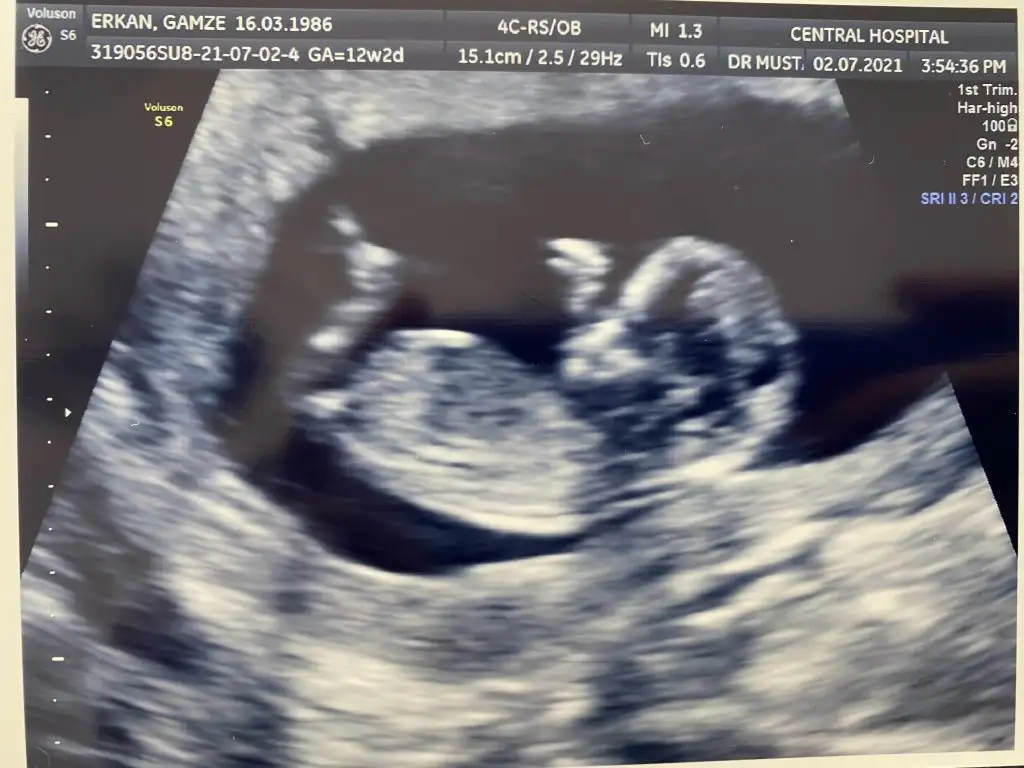

@tülperde merhaba aranıza yeni katıldım 10+2 görüntüm var bugun rica etsem yorumlarmısın

Bugün 10+2 yim kanama alanlarım var ama çok küçükmüş doktor birşey olacağını sanmıyorum dedi progestan hapa devam ediyorum bu görüntüde hala bebeğimi ayırt edemiyorum başı hangi tarafta ayakları nerde görebilen var mı